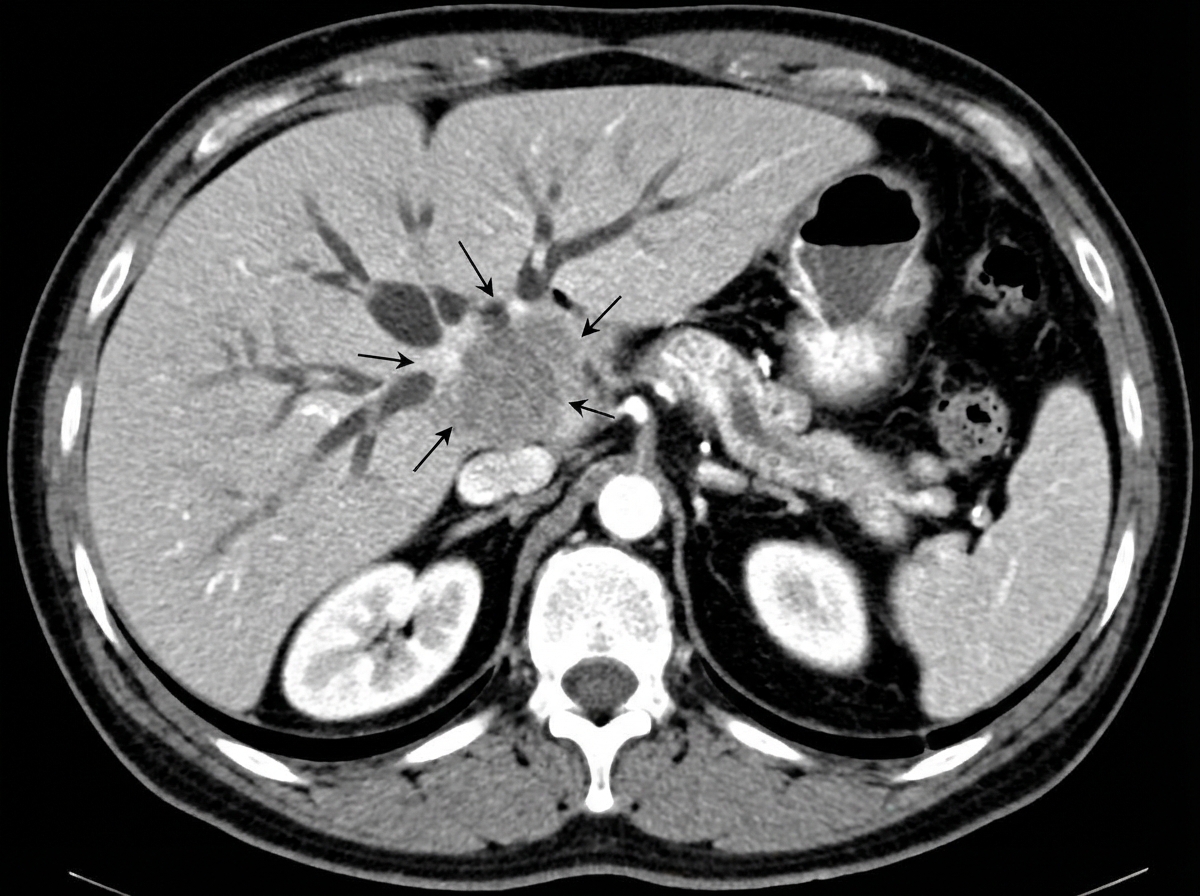

Explanation: ### Explanation The clinical presentation of fever, abdominal pain, and a hypoechoic liver lesion on imaging in an older male is highly suggestive of a **Pyogenic Liver Abscess (PLA)**. **Why Option C is the correct (False) statement:** Historically, portal vein spread (from appendicitis or diverticulitis) was the most common route. However, in modern practice, **biliary tract disease** (e.g., gallstones, strictures, or malignancy causing ascending cholangitis) has become the **most common source** of infection, accounting for 40–60% of cases. Hematogenous spread via the hepatic artery (usually from endocarditis or dental infections) is less common. **Analysis of other options:** * **Option A (True):** *E. coli* remains the most common aerobic organism isolated globally. However, *Klebsiella pneumoniae* is increasingly common, especially in diabetic patients and in Southeast Asian populations. * **Option B (True):** The **right lobe** is the most common site (involved in ~75% of cases). This is attributed to its larger size and the "streaming effect" of portal blood flow, which preferentially directs flow from the superior mesenteric vein to the right lobe. **High-Yield Clinical Pearls for NEET-PG:** * **Gold Standard Investigation:** Triple-phase CECT (shows a peripheral enhancing rim with a central non-enhancing necrotic area—the "cluster sign"). * **Most common symptom:** Fever (more common than jaundice or palpable mass). * **Management:** The mainstay of treatment is **percutaneous needle aspiration or catheter drainage** combined with long-term intravenous antibiotics. Surgical drainage is reserved for ruptured abscesses or failed percutaneous attempts. * **Amoebic vs. Pyogenic:** Amoebic abscesses are usually solitary, located in the subdiaphragmatic area of the right lobe, and present with "anchovy sauce" pus.